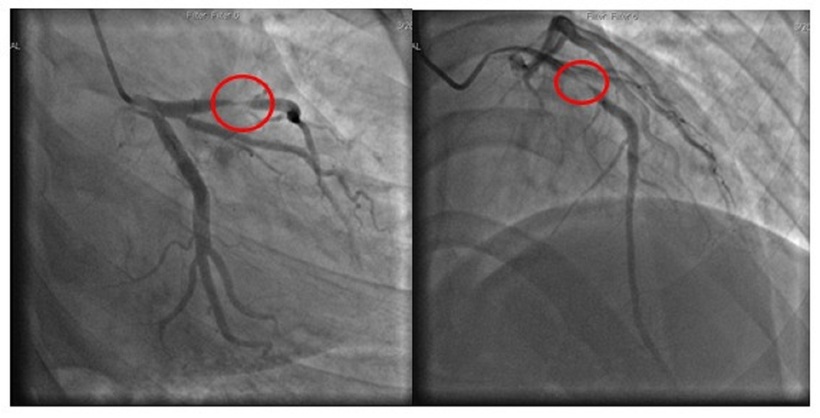

Tại bệnh viện, người bệnh được làm các xét nghiệm, điện tâm đồ, siêu âm tim và được chẩn đoán nhồi máu cơ tim cấp. Các bác sĩ đã chỉ định chụp và can thiệp động mạch vành qua da. Kết quả chụp mạch vành cho thấy hẹp 99% LAD1, ngay lập tức người bệnh được can thiệp nong bóng, đặt một stent tại vị trí động mạch bị tắc để tái thông dòng chảy.

Hình ảnh phim chụp thể hiện động mạch bị tắc. Ảnh: BVCC